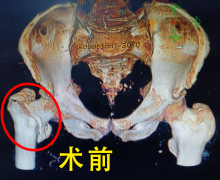

近日,我院骨科团队成功为一位91岁高龄的股骨粗隆间骨折患者实施了切开复位内固定术。术后恢复良好,患者已于1月10日在协助下下床行走,展现了在高龄患者中实施积极手术干预与

近期,新余北湖医院通过多学科协作,为一名89岁高龄的股骨颈骨折患者成功实施人工关节置换术。患者术后恢复顺利,如期实现下床行走,展现了医院在高龄骨科疾病救治方面的综合